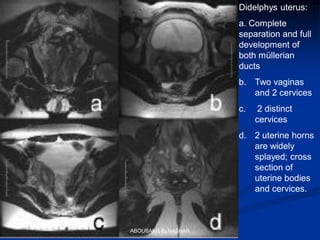

Didelphys uterus:

a. Complete

separation and full

development of

both müllerian

ducts

b. Two vaginas

and 2 cervices

c. 2 distinct

cervices

d. 2 uterine horns

are widely

splayed; cross

section of

uterine bodies

and cervices.